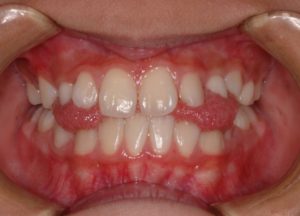

上顎前突🔸出っ歯な噛み合わせ

交叉咬合🔸上の歯と下の歯が交叉(クロス)したような噛み合わせ

開口🔸上の歯と下の歯で噛んだ際(咬合した際)に前歯が開いている噛み合わせ

舌が入る隙間があるのがわかりますか?💡

正中離開🔸前歯の1番目の歯が左右に離れる(離開する)

の原因となる事があります🦷